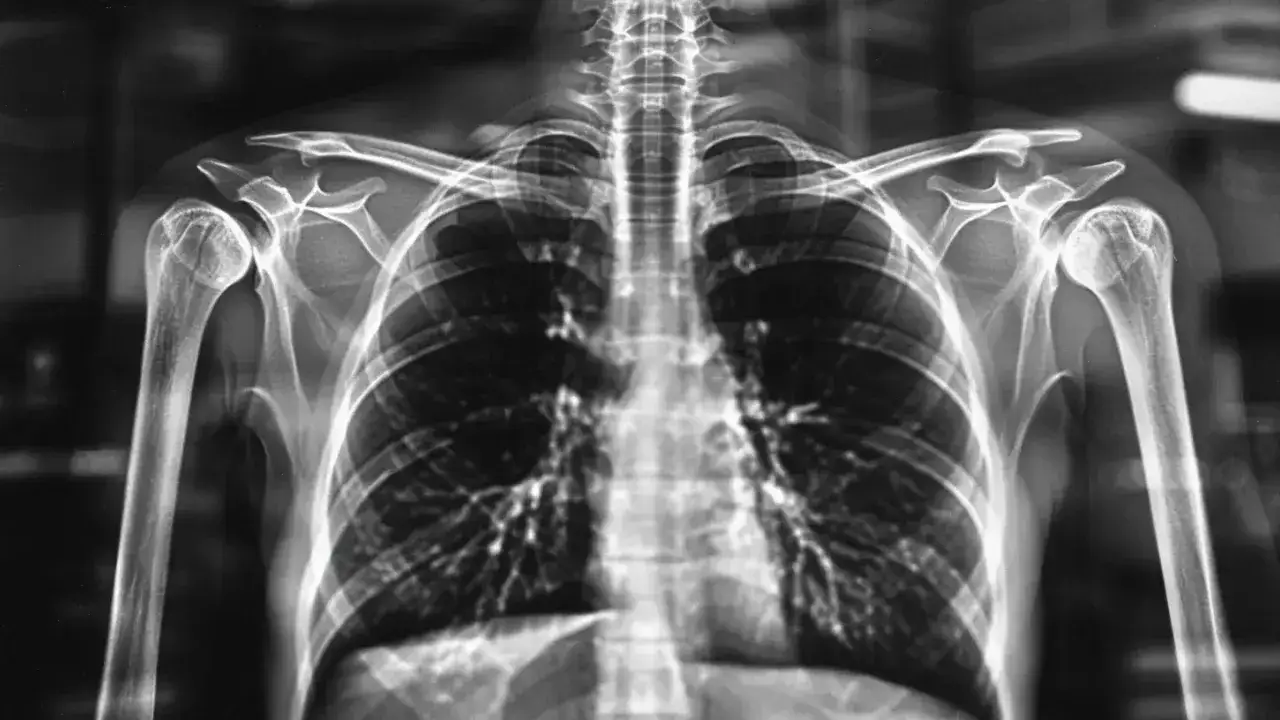

Diagnoza infekcji pasożytniczej płuc wymaga przeprowadzenia szeregu specjalistycznych badań. Lekarz rozpoczyna od wywiadu medycznego i osłuchiwania płuc. Następnie zleca odpowiednie testy diagnostyczne.

Wykrycie pasożytów w płucach często wymaga zastosowania kilku metod diagnostycznych jednocześnie. Badania obrazowe pozwalają ocenić stan płuc, podczas gdy testy laboratoryjne potwierdzają obecność pasożytów.

1. Badanie rentgenowskie klatki piersiowej - uwidacznia zmiany w płucach 2. Tomografia komputerowa - dokładniejszy obraz zmian chorobowych 3. Badanie plwociny - wykrywa larwy i jaja pasożytów 4. Badania krwi - sprawdza poziom przeciwciał 5. Badanie kału - identyfikuje obecność pasożytów 6. Bronchoskopia - pozwala na bezpośrednią obserwację dróg oddechowychJak przebiega badanie u specjalisty?